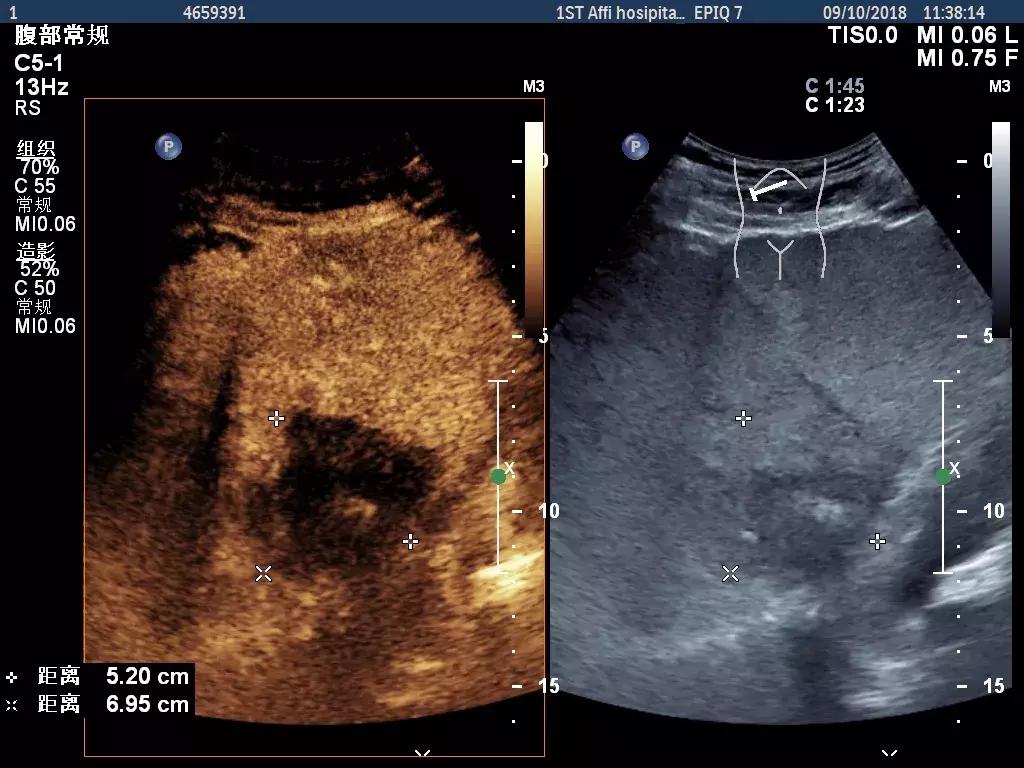

2D:右肝内可见一低回声结节,大小约5.6*4.4*5.7cm。

超声造影:经外周静脉注入声诺维2.4ml,右肝结节动脉期可见稀疏增强,稍高于周边实质回声,门脉期消退,后期消退明显。

超声造影静态图